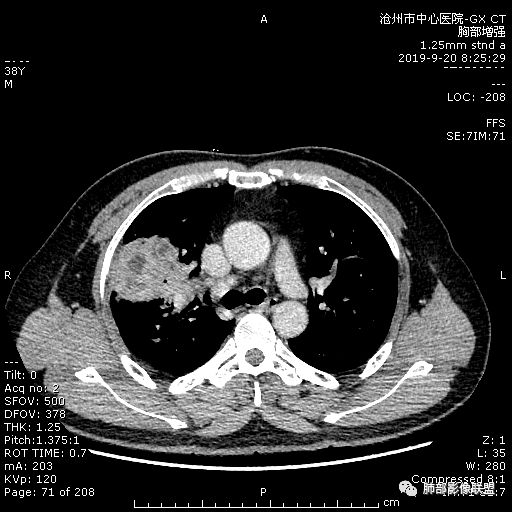

年轻男性,咳嗽2月,痰中带血,胸痛,炎症指标稍高,肿标正常。影像,右肺上叶不规则团块影,浅分叶,伴边界不清磨玻璃影,从外周向内分布,局部胸膜增厚,病灶中央坏死,坏死边界尚清,空洞形成,空洞内壁光滑;考虑炎性肉芽肿性病变,结核可能,鉴别恶性肿瘤及真菌感染。病灶分布特点不考虑隐球。

右肺上叶不规则病灶,密度不均,有分叶,边缘不清,中央有坏死,坏死壁尚光滑,增强壁有强化,病灶有外朝内,整体收缩为主,慢性病程,考虑炎性病变,肺脓肿或者结核,淋巴结肿大,支气管截断,胸膜脂肪间隙变窄,加个鉴别恶性肿瘤。

38岁,男性,慢性咳嗽2月,右胸痛8天,无发热;白细胞高,肿瘤标志物不高;右上肺不规则块状影,周围有磨玻璃影,边界清,整体有膨胀感,分叶,与胸膜糊墙,并见栽赃,增强肿块中央坏死,周边强化。综合考虑,考虑恶性,鳞癌可能。

38岁,男性,慢性咳嗽2月,右胸痛8天,无发热。白细胞高,肿瘤标志物不高。右上肺不规则块状影,周围有磨玻璃影,边界模糊,整体有膨胀感,分叶,与胸膜糊墙,可疑栽赃,增强肿块中央坏死,边界清,周边强化明显,强化区有低密度影,壁不规则,跨叶生长,支气管截断,伴支气管扩张,综合考虑腺癌

中年男性,咳嗽2月,伴胸痛8天,少许痰血,无发热中性粒明显增高,低氧,肿标不高,右肺上叶不规则实性肿块,深分叶,局部凹陷呈月牙铲改变,多坏死,多空泡,前段支气管分支似见堵塞,2R、4R、10R和7区淋巴结肿大。考虑肺癌可能,建议支气管镜活检

晨读:右肺上叶不规则团块,深分叶,膨胀为主,有部分收缩,叶间裂牵拉上移,内多液化坏死,有支气管扩张,右肺上叶大支气管近端通畅,远端堵塞,说明肿块来源于外周,纵隔及右肺门淋巴结肿大,胸膜糊墙为主,年轻人,肿标不高,炎性指标高,综合考虑炎性肉芽肿放前面脓肿,结核,肿瘤放后面。

首先病灶示:跨尖、后、前三段,局部突入中叶;大家理解一下:是不是光滑的地方有叶裂,毛糙的地方没叶裂。

宽基底,胸膜增厚

炎性病变一定有

但是深分叶,坏死部分内壁不清

近端支气管堵塞

肺门淋巴结肿大

恶性一定不能除外